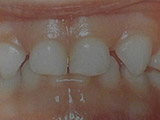

Ουλίτιδα

Η νόσος της ουλίτιδας:

- Εκδηλώνεται με διόγκωση και ερυθρότητα των ούλων γύρω από τα δόντια.

- Το κυριότερο χαρακτηριστικό είναι η αιμορραγία των ούλων στο βούρτσισμα και ορισμένες φορές συνοδεύεται από πόνο και κακοσμία του στόματος.

- Οφείλεται, όπως και η τερηδόνα, στη μικροβιακή πλάκα δηλαδή στα μικρόβια που προσκολλώνται στα δόντια και τα οποία έρχονται σε επαφή με τα ούλα προκαλώντας τοπικά φλεγμονή.

- Μπορεί εύκολα να προληφθεί με σωστό και καθημερινό βούρτσισμα των δοντιών, τη χρήση οδοντικού νήματος και των στοματικών διαλυμάτων σύμφωνα με της οδηγίες του παιδοδοντίατρου. Σημαντικός είναι επίσης ο τακτικός έλεγχος των δοντιών στον παιδοδοντίατρο και ο καθαρισμός των δοντιών 1-2 φορές το χρόνο.